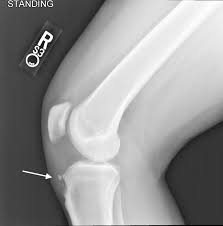

Knee disease osgood schlatters in adults. In four cases a true joint had formed between an ossicle in the patellar ligament and a facet on the tibia. Osgood-Schlatter disease is a painful condition causing inflammation just below the knee. The tendon below your kneecap called the patellar tendon attaches to the tibial tuberosity on the shinbone called the tibia.

Osgood Schlatter disease or Osgood Schlatter lesion is a very common cause of knee pain in children between the ages of 10 and 15 years old. An adhesive tape is placed across the part of the bone that is tender and swollen the tibial tuberosity while the patients knee is bent. Osgood-Schlatter is a common disease with most cases resolving spontaneously with skeletal maturity.

Friday April 05 2019. Pain that gets worse with exercise or activity. Seven adults with the sequelae of Osgood-Schlatters disease presented after experiencing symptoms for an average of eight years. Osgood Schlatter disease symptoms. Osgood-Schlatter exercises are used to strengthen the muscles around the knee joint principally the quadriceps hamstrings and gastrocnemius muscles. Common in adolescents during growth spurts Osgood-Schlatter disease can affect adults if not properly assessed and treated. Pain and tenderness in front of the knee. This bony protrusion is called the tibial tuberosity. Adults with continued symptoms may need surgical treatment if they fail to respond to conservative measures.